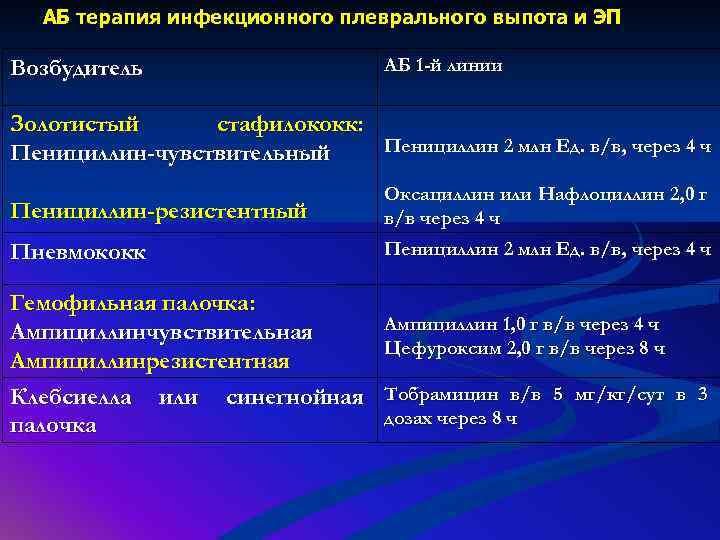

Дифференциальная диагностика заболеваний плевры